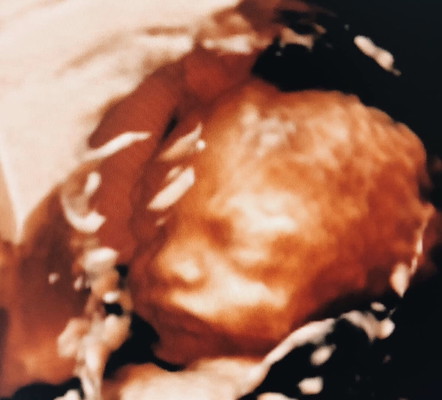

เข้าใจอารมที่ว่า ลูกใคร ใครก็รัก ก็หลงแล้ว นี้ขนาดอยู่ในท้องยังหลงขนาดนี้

แอบอิจฉาจังค่ะบ้านนี้ซาว4มิติ3รอบแล้วน้องคว่ำหน้าไม่ยอมให้แม่เห็นเลยคิดเเล้วน้อยใจ🤣🤣🤣🤣🤣